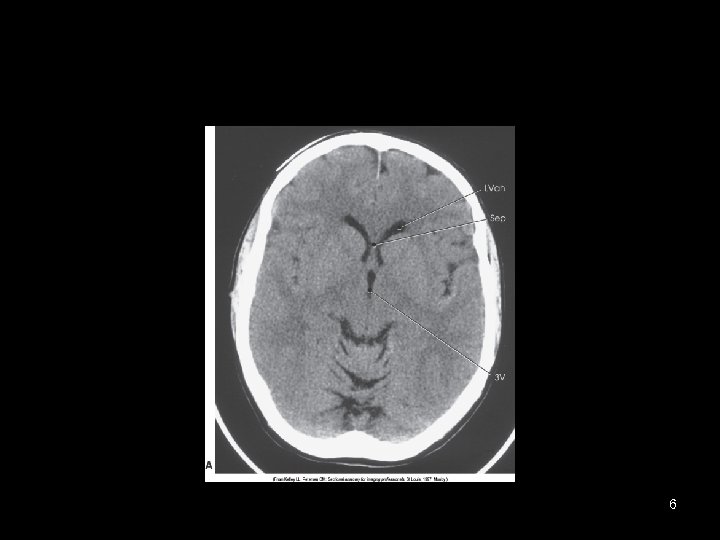

6